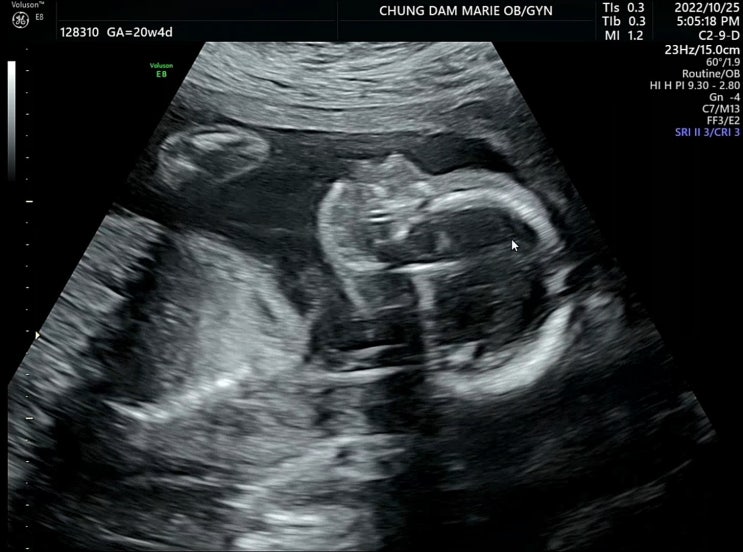

23주 1일차 (11/12. 토) 서울성모병원 두 번째 입원 - 첫째 날 청담마리산부인과에서 서울성모병원으로 전...